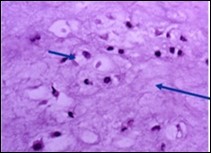

Distinction between benign cartilaginous lesions and atypical cartilaginous tumour or grade 1chondrosarcoma (ACT/CS1) can be challenging, Typically, benign cartilaginous lesions are hypo-cellular, in contrast to hyper-cellular atypical cartilaginous tumour or grade 1 chondrosarcoma 5, 6. Figure 1, Figure 2, Figure 3, Figure 4, Figure 5, Figure 6, Figure 7, Figure 8.

Figure 8.Enchondroma delineating hyaline cartilaginous cells with vacuolated cytoplasm and uniform nuclei 16.